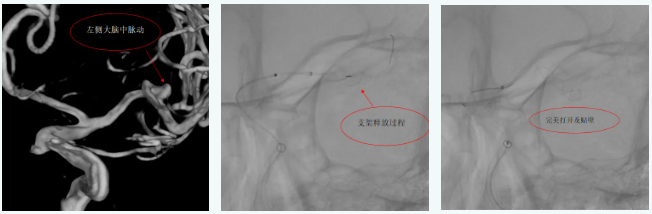

病例2

患者左侧大脑中动脉动脉瘤,使用血流导向装置,支架完美打开及贴壁,术后3天顺利出院。